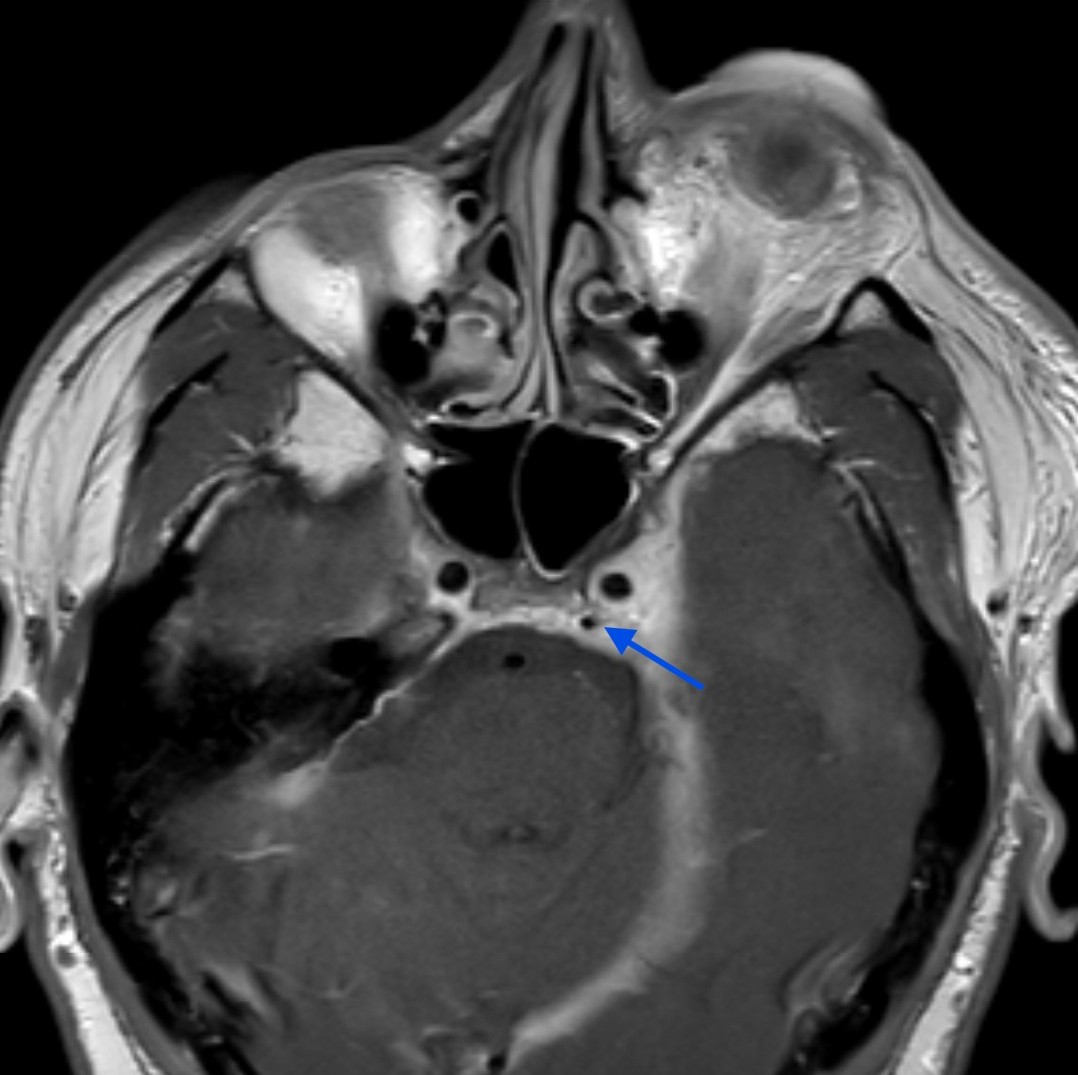

Orbital compartment syndrome (OCS) is an ophthalmologic emergency due to an acute rise in intra-orbital pressure and can result in permanent vision loss, oftentimes requiring emergent surgical decompression. Orbital compartment syndrome most commonly occurs due to recent trauma and is often easily diagnosed by history and physical exam. However, there are other causes of OCS where a more subacute/chronic rise in pressure can lead to an atypical presentation. This is a case report of a 48-year-old male who presented with left eye pain and swelling for the past 6 months. The patient had seen two ophthalmologists prior to his emergency department (ED) presentation who had prescribed him an antibiotic ointment, oral steroids, and steroid eye drops. The physical exam in the ED was concerning for increased intra-ocular pressure (IOP) and decreased vision. Ophthalmology was consulted and requested magnetic resonance angiography (MRA) to assess a vascular etiology given tortuous retinal vasculature. Emergent surgical decompression was deferred due to chronicity of symptoms, and patient was started on dorzolamide/timolol and brimonidine eye drops as well as intravenous (IV) acetazolamide with subsequent improvement in IOP. Imaging revealed a left carotid-cavernous sinus fistula (CCF), and the patient was admitted to neurosurgery. Patient successfully had an embolization with subsequent normalization of IOP and improvement of symptoms. This case is a good example of how non-traumatic causes of OCS can lead to misdiagnosis and how surgical decompression could potentially be deferred in subacute OCS.